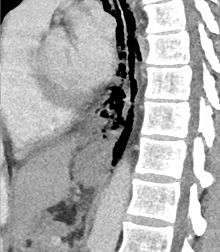

Sagittal remormatted CT image showing discontinutity in the wall of the posterolateral aspect of the distal esophagus

The diagnosis of Boerhaave's syndrome is suggested on the plain chest radiography and confirmed by chest CT scan. The initial plain chest radiograph is almost always abnormal in patients with Boerhaave's syndrome and usually reveals mediastinal or free peritoneal air as the initial radiologic manifestation. With cervical esophageal perforations, plain films of the neck show air in the soft tissues of the prevertebral space.

Hours to days later, pleural effusion(s) with or without pneumothorax, widened mediastinum, and subcutaneous emphysema are typically seen. CT scan may show esophageal wall edema and thickening, extraesophageal air, periesophageal fluid with or without gas bubbles, mediastinal widening, and air and fluid in the pleural spaces, retroperitoneum or lesser sac.